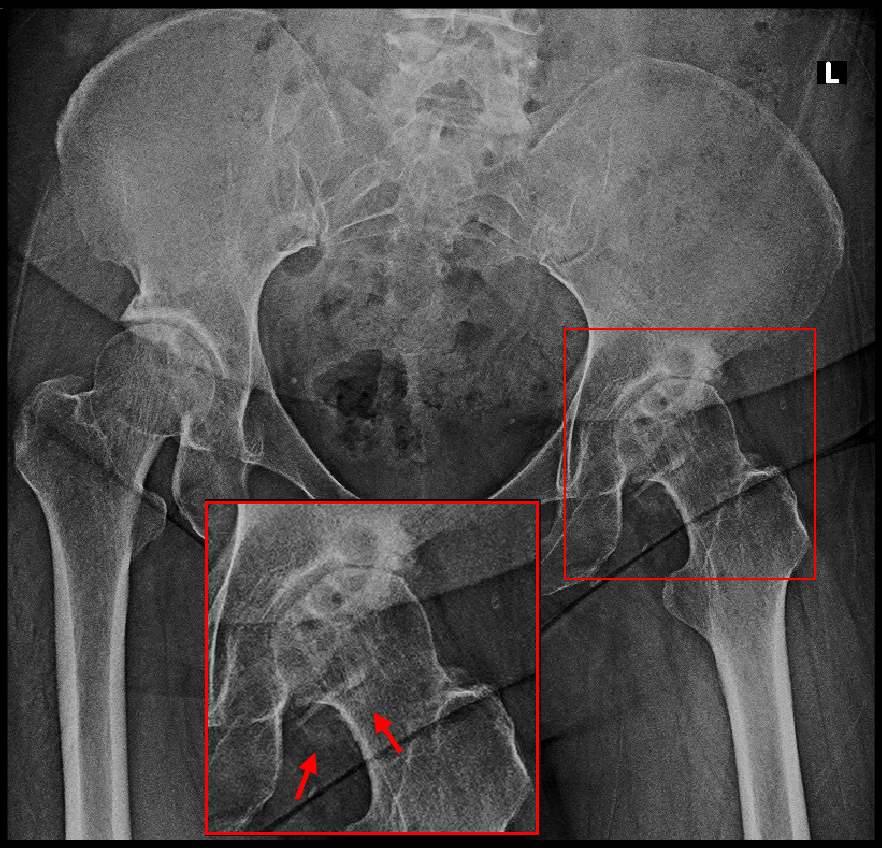

下図の変形性股関節症の患者さんは、72才の男性で10年前から右腰痛と股関節痛があり、多くの整形外科を受診したけれど、腰に起因する症状として治療されてきて良くならなかったそうです。

医大を受診して初めて股関節に起因する症状と診断されたそうですが、医大では「手術するほどの症状でないから、様子をみて、手術したくなったらまた受診してください。」と言われ、何も治療はしてくれなかったと言っていました。割り切った姿勢とも言えますが、患者さんとしては切ない思いを持っても仕方ないでしょう。

医大診断OA 1.png